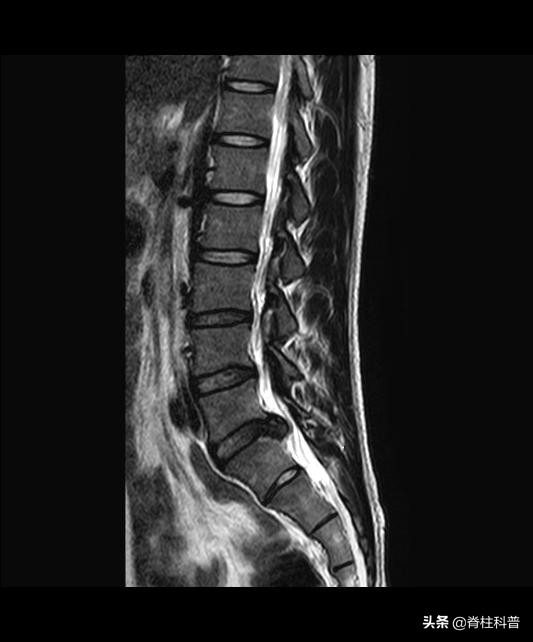

腰椎间盘摘除术是目前一个较为成熟、有效的外科手段。然而腰椎间盘突出症具有复杂的病因及影像学特点,手术难度大,术后复发导致腰腿疼痛在临床上仍然非常常见,给患者的身心和经济带来极大的负担。

部分患者在术后6个月或者更长时间无症状期或明显缓解期之后,由同一或临近椎间盘间隙再次发作(发作原因不同)导致腰腿疼痛等症状的出现,临床上称之为腰椎间盘突出症术后复发。上一篇科普文有提过,有研究指出,腰椎间盘突出症术后复发率为5%~15%,是术后的常见远期并发症,严重影响手术效果,也是难倒许多脊柱外科医师的问题之一。